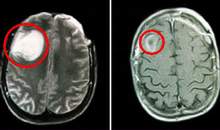

U nguyên bào thần kinh là u ác tính của hệ thần kinh giao cảm hay gặp ở trẻ em. Đây là loại ung thư đứng hàng thứ 4 trong các loại bệnh ung thư hay gặp ở trẻ em sau bệnh bạch cầu cấp, u não và u lympho. Bệnh thường biểu hiện bằng những triệu chứng như thế nào? TS Phùng Tuyết Lan-Phó Trưởng Khoa ung bướu-BV Nhi TW trả lời phỏng vấn của phóng viên VOV2. (Y tế)